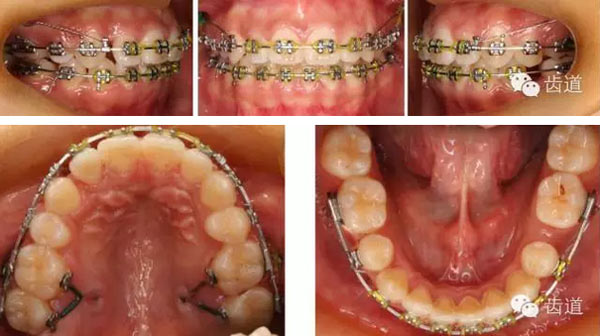

矯治過(guò)程

矯治結(jié)束后口內(nèi)像